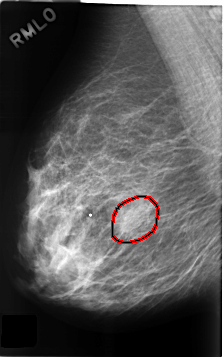

C_0313_1.RIGHT_MLO

FILE: C_0313_1.RIGHT_MLO.OVERLAY

TOTAL_ABNORMALITIES 1

ABNORMALITY 1

LESION_TYPE MASS SHAPE OVAL MARGINS OBSCURED

ASSESSMENT 4

SUBTLETY 3

PATHOLOGY BENIGN

TOTAL_OUTLINES 1

BOUNDARY